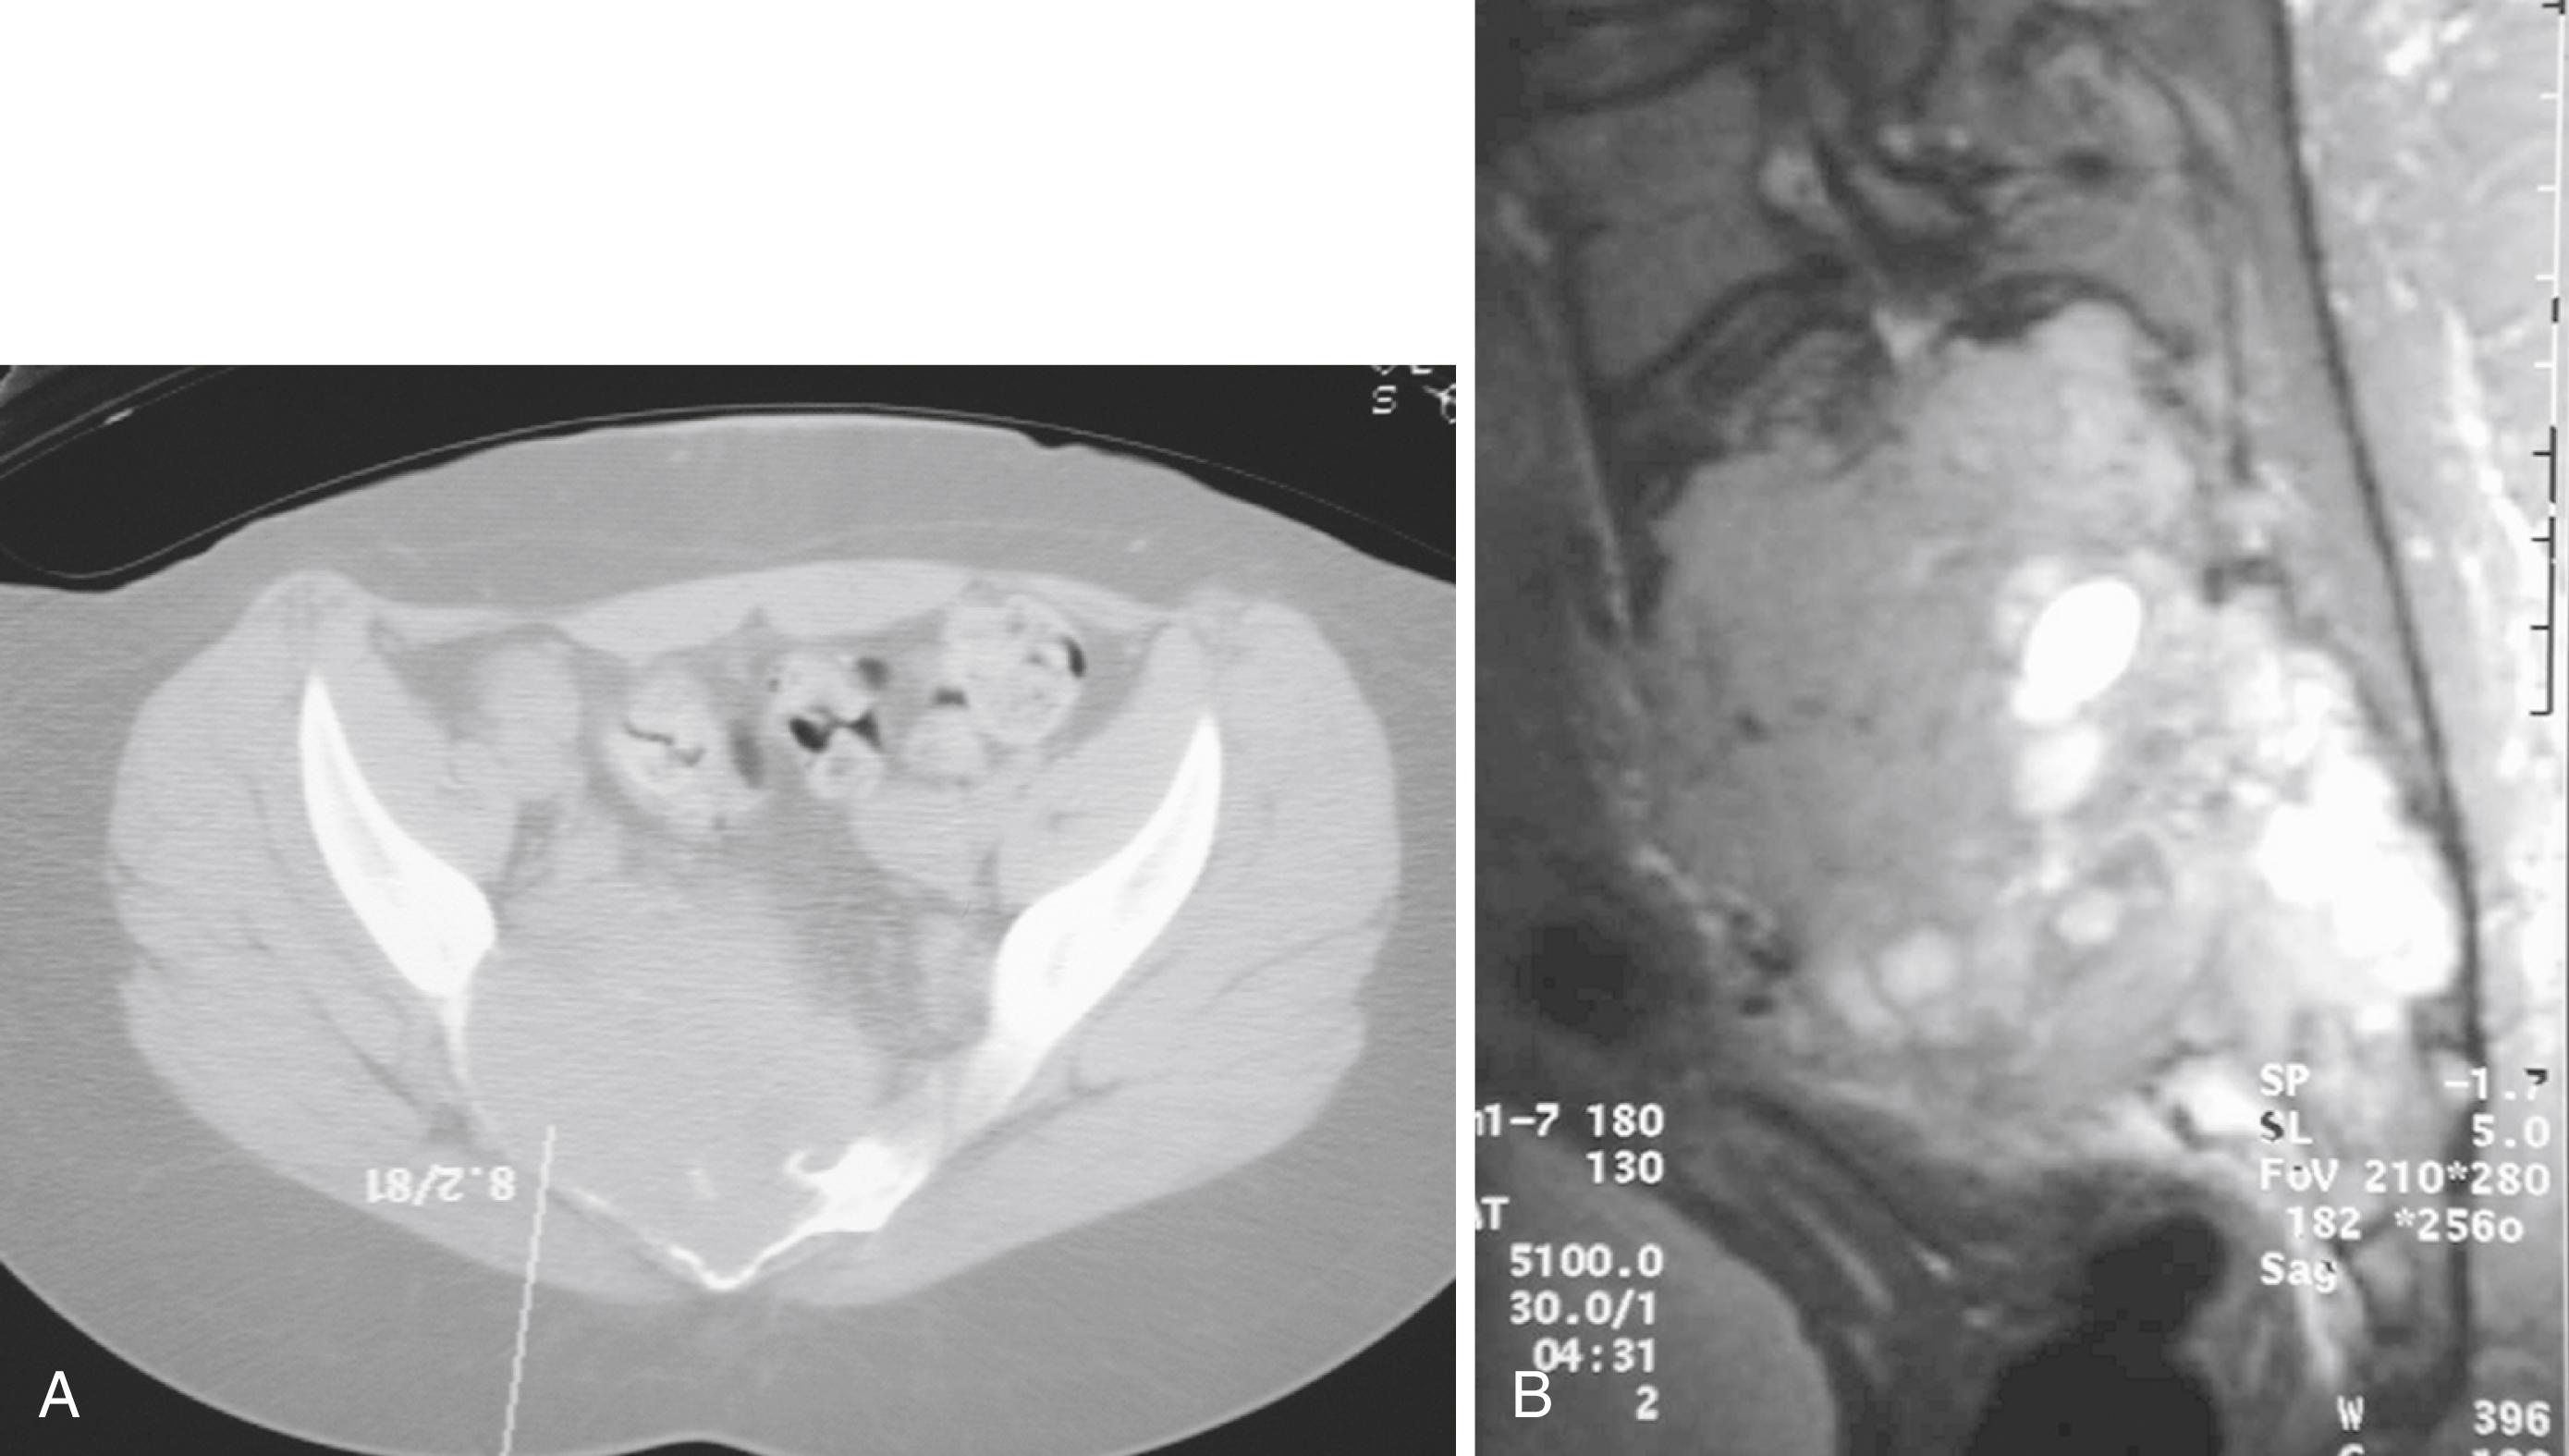

Radiographically, LCH can have various appearances. Marked flattening of the vertebral body, or vertebra plana, is a common manifestation. Although LCH is the most common cause of vertebra plana ( Fig. 26.17 ), other disease processes should be considered in the differential diagnosis if the clinical situation warrants. Other causes of vertebra plana include Ewing sarcoma, lymphoma, leukemia, Gaucher disease, aneurysmal bone cyst, and infection. In flat bones, the lesions usually are well circumscribed, “punched-out,” purely lytic lesions. The lesions may have a “hole within a hole” appearance because of different involvement of the two tables. In the diaphyses of long bones, the lesions may have an aggressive permeative appearance with periosteal reactive bone formation ( Fig. 26.18 ). This appearance may resemble Ewing sarcoma, infection, or lymphoma. A bone scan may help identify additional lesions, but approximately 30% of scans may be falsely negative. A skeletal survey is more effective for this purpose.

FIGURE 26.17, Eosinophilic granuloma of vertebral body.